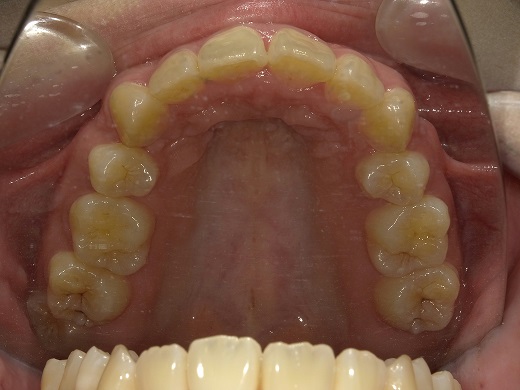

治療前上顎